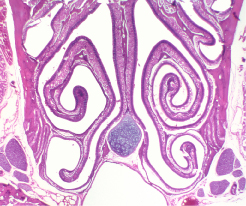

This Concept Map, created with IHMC CmapTools, has information related to: Respiratory3, Fibrocytes secrete Elastin, Group of organs performing specific Physiological Functions, Lamina Propria embedded with Glands, Trachea branch into Bronchi, Nerves visceral efferents Parasympathetic, Respiratory Epithelium rests on Lamina Propria, Basal characteristicized by Desmosomes, Bronchi branch further into Bronchioles, Sustenacular characterized by Columnar, Pneumocytes include Type I, Nasal Cavity from the Oral Cavity, Lungs contain Respiratory Bronchioles, Brush rich in Cytoskeleton, Respiratory System comprised of Conducting Portion, Pleura both Parietal, Mesothelium is Simple Squamous-->Cuboidal Epithelium, Respiratory Epithelium cell types Neuroendocrine APUD, Paranasal Sinuses lined by Respiratory Epithelium, Conducting Portion conduct air to Lungs, Respiratory Epithelium cell types Brush